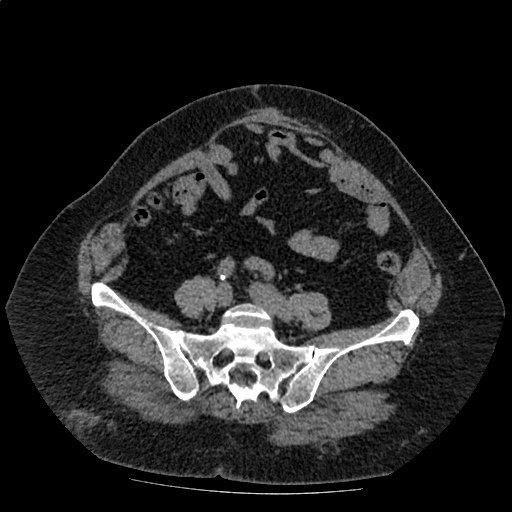

В другой больнице пациентке была выполнена IPOM-пластика по поводу пупочной грыжи. Но, что то пошло не так. Сетка инфицировалась и ее удалили уже через открытый разрез. Конечно же пациентка считает, что ей инфекцию "занесли" (но об этом в отдельном посте).

Грыжевой выпячивание естественно вернулось, ещё в худшем варианте.

Максимальная ширина дефекта 12 см.

Пациентка с лишним весом, но попытки снижения веса безуспешны.

Итого: пациентка с лишним весом, с рецидивной грыжей, с лапаротомией, грыжа большого размера (W3), шириной 12 см.